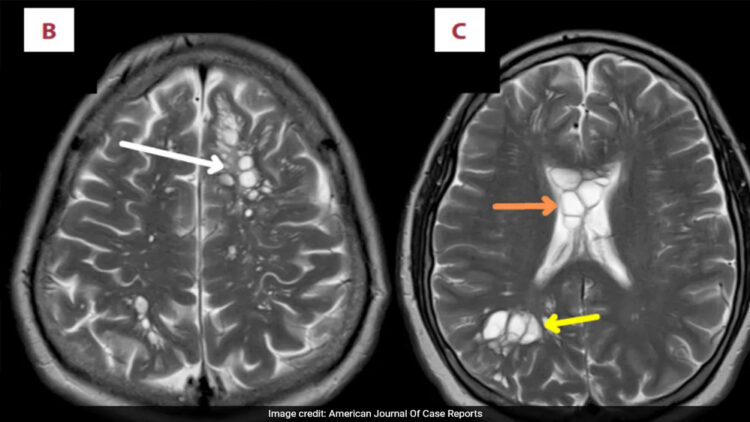

കഠിനമായ മൈഗ്രൻ ബാധിച്ച് ആശുപത്രിയിൽ എത്തിയ 52 കാരന്റെ തലച്ചോറിൽ നാടവീരകൾ കണ്ടെത്തി. ന്യൂയോർക്ക് പോസ്റ്റിന്റെ റിപ്പോർട്ട് അനുസരിച്ച് യുഎസ് പൗരനായ വ്യക്തിക്ക് കഴിഞ്ഞ നാല് മാസമായി തലവേദന അനുഭവപ്പെട്ടിരുന്നു. വേദന തീവ്രമായതൊടെ അദ്ദേഹം വൈദ്യസഹായം തേടി. സ്കാനിംഗിൽ തലച്ചോറിന്റെ ഇരുവശത്തുമായി ഒന്നിലധികം മുഴകൾ കണ്ടെത്തി, പിന്നീട് പരിശോധനയിൽ നാടവിരകളാണെന്ന് വ്യക്തമായി. രോഗിയെ ഉടൻ തന്നെ തീവ്രപരിചണ വിഭാഗത്തിലേക്ക് മാറ്റി ആദ്യ പടിയായി തലച്ചോറിലെ നീക്കം കുറയ്ക്കാനുള്ള ചികിത്സ ആരംഭിച്ചു.

ജന്തുക്കളുടെ ചെറുകുടലിൽ അധിവസിക്കുന്ന ഒരിനം പരാദ വിരയാണ് നാടവിര. ഇത്തരം വിരകൾ തലച്ചോറിൽ കണ്ടെത്തുന്നത് അത്യപൂർവ്വമാണെന്ന് അടുത്തിടെ പ്രസിദ്ധീകരിച്ച അമേരിക്കൻ ജേണൽ ഓഫ് കേസ് റിപ്പോർട്ടിൽ പറയുന്നു. യുഎസിൽ ഇത്തരം രോഗബാധ അധികം കണ്ടെത്തിയിട്ടില്ല.